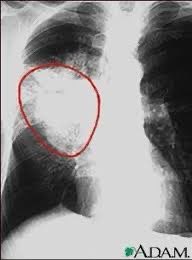

والإصابة بسرطان الرئة؛ حيث يُعدّ التدخين السبب المباشر لمعظم حالات سرطان الرئة .

الإصابة بمرض الانسداد الرئوي المزمن COPD

ويعتبر اهم مسبب لالتهاب القصبات الهوائية المزمن : Chronic bronchitis

التي تسبب الكحة المزمنة وضيق النفس تتيجة الالتهابات المستمرة في القصبات الهوائية فتضيق وتمتليء بالسوائل والخلايا الالتهابية